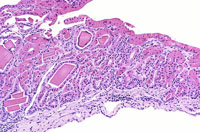

Eosinophilic crystalline inclusions and hyalin degeneration of epithelial cytoplasm in an adenomatous hyperplasia of the gallbladder. High magnification shows the brightly eosinophilic hyalinized cytoplasm of the epithelial cells.